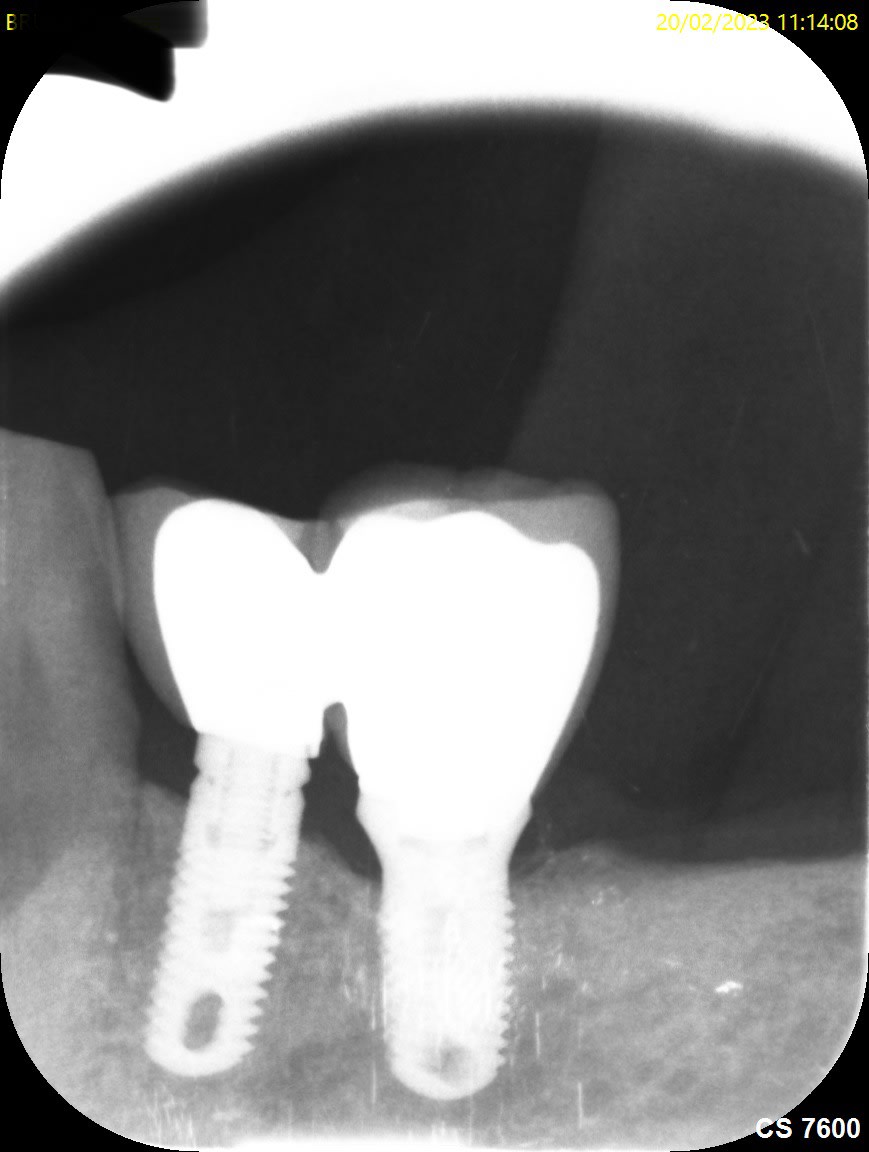

Bonsoir pourriez vous m’aider pour la marque de ces implants je pense à du zimmer tsv pour les implants en position de 4…je pense que les implants distaux sont des zimmer aussi car posé par le même praticien mais j’ai l’impression que ce sont des tissus level est ce que la connectique est identique?

Pour les premo c’est des TSV, et les molaires des AdVent zimmer pour les 2….

Connexion différente, hex interne pour les TSV, octogonale comme des straumann pour les AdVent